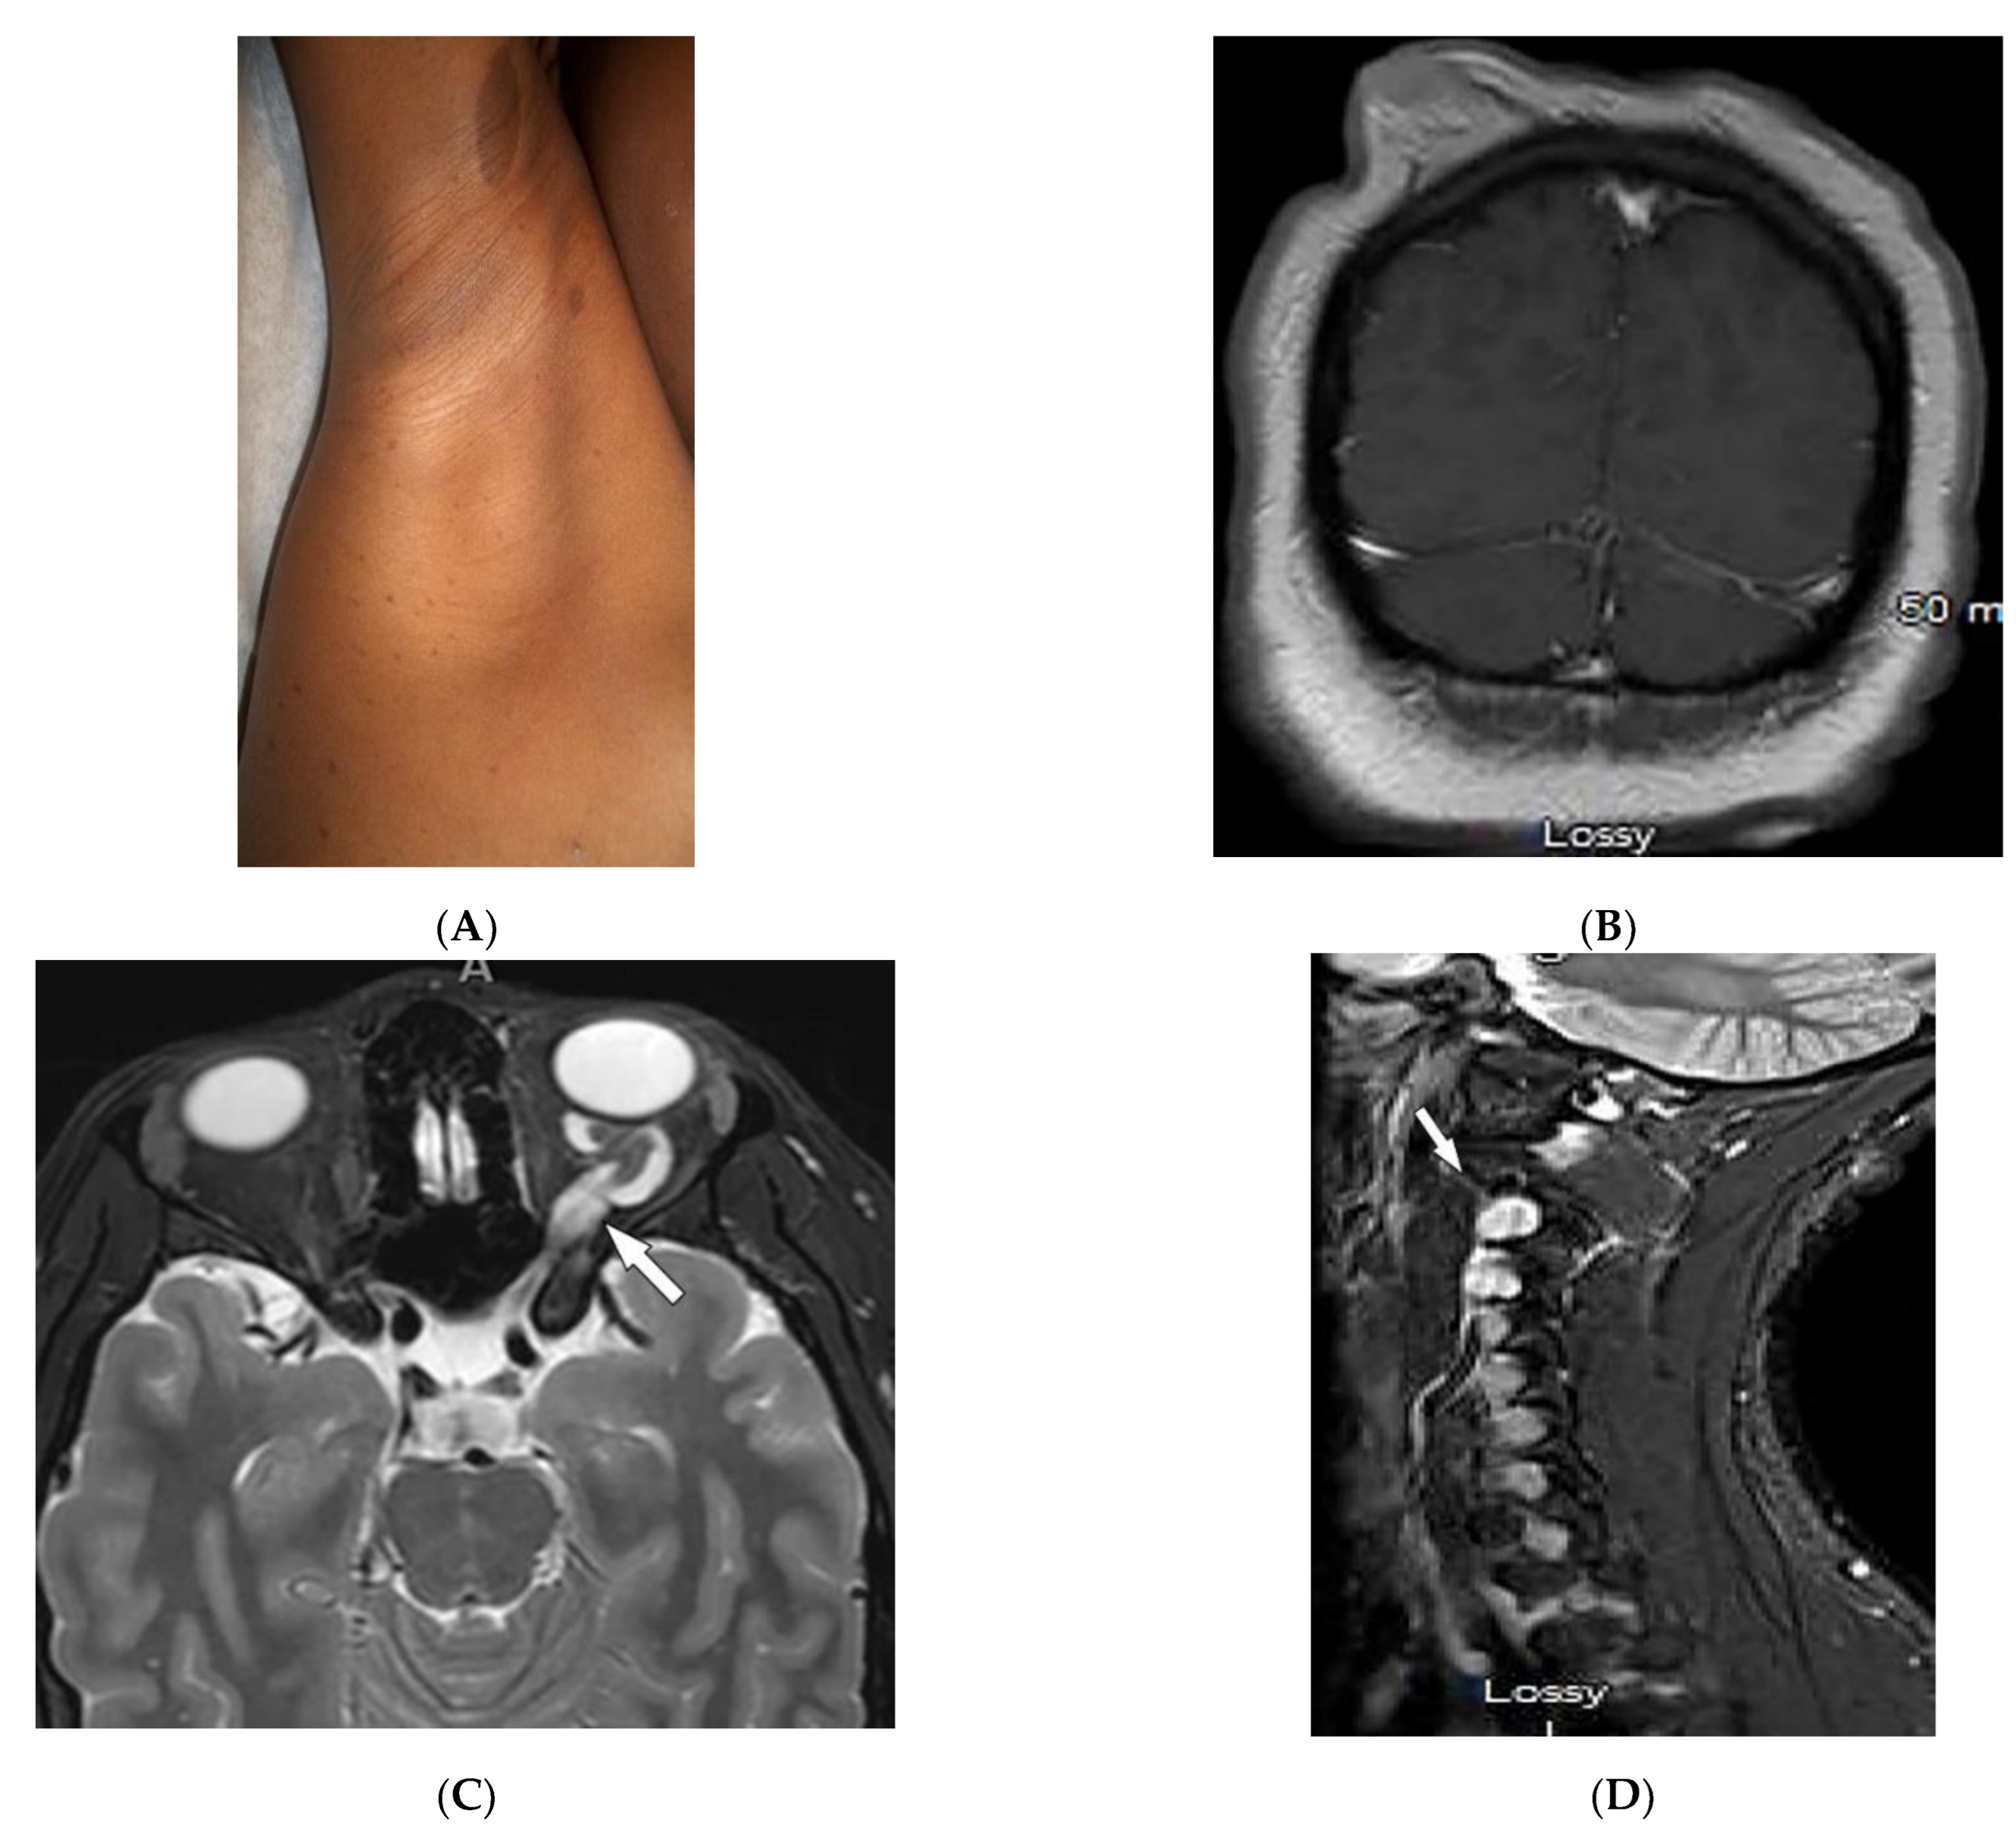

| Neurofibromatosis type 1 (NF-1) | Café-au-lait spots Freckling (axillary or inguinal) Lisch nodules Neurofibromas Optic nerve and other gliomas Skeletal abnormalities | Peripheral nerve sheath tumors including cutaneous, spinal, plexiform neuroma Diffuse thickening of the nerve |

3.2. Neurofibromatosis Type 1